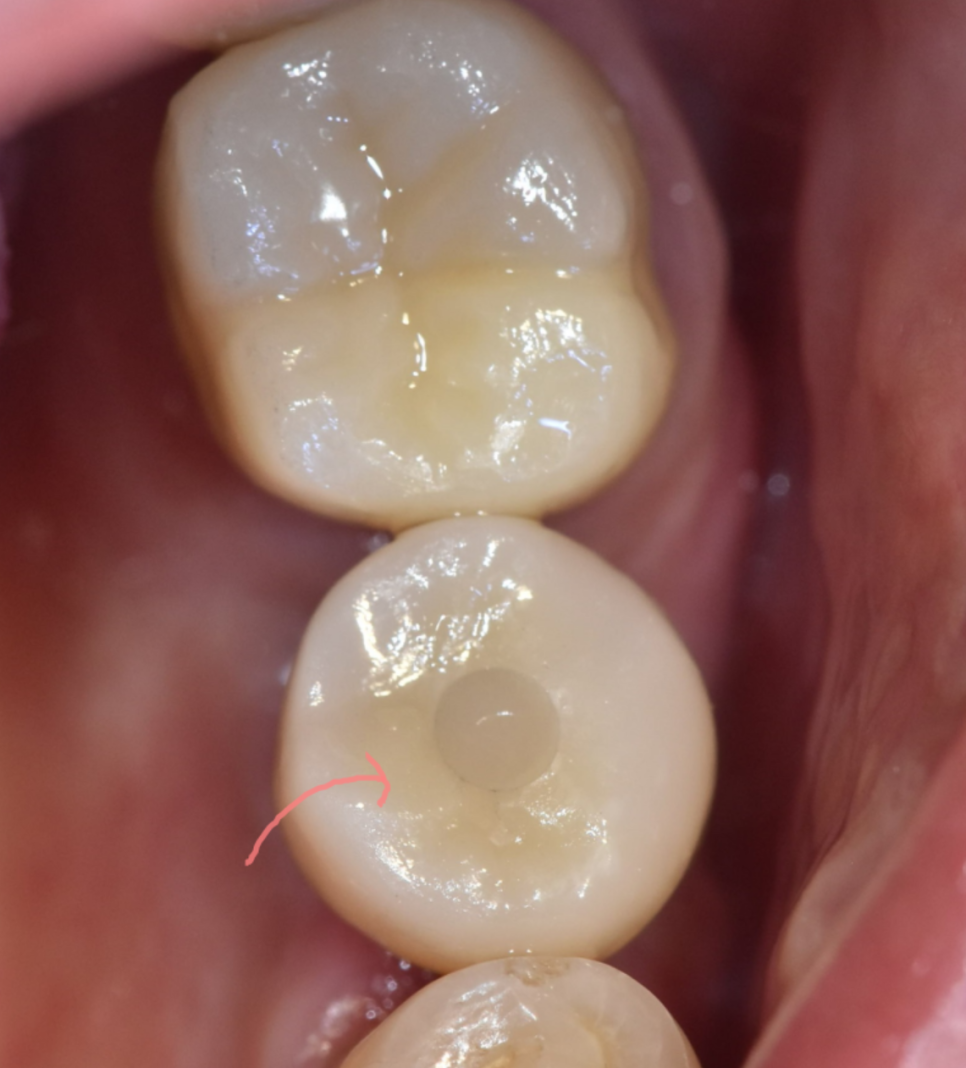

골 유착이 단단히 된 것이 확인되면

보철물을 제작하는 단계로 넘어갈 수 있어요.

실제로 식사할 수 있는 인공치아를 만드는 과정입니다.

이 때는 단순히 모양만 구현하는 것이 아닙니다.

주변 치아와의 조화, 색상까지 고려

정밀하게 설계됩니다.

보철물까지 올라갔다면 끝...?

우선, 정기적인 검진은 필수입니다.

처음에는 1달 뒤에 확인을 하게 되고

그 뒤부터는 3개월, 6개월, 1개월

점차 기간이 늘어나게 됩니다.

임플란트 구멍 메꿔드린게 잘 붙어있는지

나사가 풀리진 않았는지

염증은 없는지